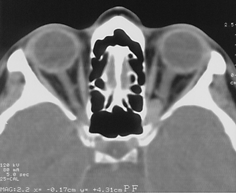

Менингиомы ольфакторной ямки (рис. 3)

Развиваются в области продырявленной пластинки, петушиного гребня и крыши решетчатой кости, часто распространяются кзади на площадку основной кости.

Рисунок 3. Менингиома ольфакторной ямки (КТ с контрастным усилением)

Они могут располагаться симметрично относительно средней линии или распространяться преимущественно в одну сторону, часто сочетаются с гиперостозом. Эти новообразования характеризуются длительным бессимптомным периодом. В некоторых случаях опухоли гигантских размеров проявляются лишь умеренной лобной психопатологической симптоматикой, нарушениями обоняния и застойными дисками зрительных нервов. Опухоль может распространяться экстракраниально в решетчатую пазуху, медиальные отделы глазниц, носоглотку.